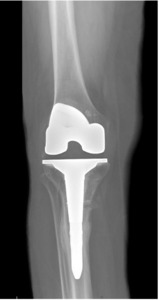

Quantitative range-of-motion and outcome-score data are summarized in Table 1. At the two-week clinic visit the incision was fully healed and sutures were removed. The patient continued full weight bearing in the brace. By six weeks the osteotomy displayed bridging callus across the osteotomy site (Figure 6), the brace was discontinued, and she achieved an unrestricted gait pattern without assistive devices. Four months after surgery, the patient had resumed activities such as tennis and reported no pain or swelling. Radiographs at that time demonstrated complete cortical union without any interval changes in alignment (Figure 7). At the nine-month assessment she reported hiking up to five miles and skiing on groomed slopes without limitation. Imaging showed continued consolidation of the osteotomy and stable components (Figure 8).